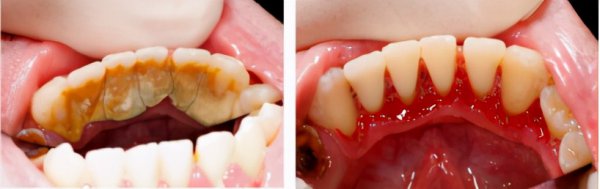

在它刚开始成长的阶段,认真刷牙,配合牙线、漱口水是可以把它消灭的,可它一旦长大,也就是钙化了,就会成为一个无赖恶霸,刷牙就没辙了,要超声波洗牙,这个可是牙结石的天敌。

此外,洗牙不光是消灭牙结石,还能获得自己牙齿健康信息,比如是否有蛀牙,智齿等,而且洗牙后口气都会变清新,牙龈也不出血了。一句话:洗牙不伤牙,不洗牙才伤牙。

龈上牙结石,也叫可见牙结石,一般是覆盖在牙缝、牙背、牙根部,肉眼能看到。

龈下牙结石,也叫不可见牙结石,这种牙结石已经侵入到了牙龈下了,一般伴随有牙龈出血,肉眼不能看到。

0度:无软垢及牙结石。

1度: 少许软垢或牙结石,但未超过牙面的l/3。

2度:有牙结石,未超过冠面的1/3,有少量的龈下结石。

3度:牙结石不超过冠面的2/3,有较多的龈下结石。